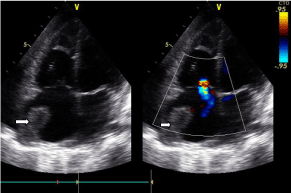

She had multiple infiltrative masses in the lateral walls of the right ventricle and left ventricle with poor contractility of the ventricles. She had a large fixed mass in the right atrium. Both parietal and visceral pericardia were thickened with thick pericardial effusion. There was involvement of the lateral wall of the left ventricle with sentinel lesion at the hinge of the mitral valve (Figure 2 and Figure 3).

Figure 2: An image showing the tumor at the roof of the right atrium (arrows) and mild regurgitation of tricuspid valve. View Figure 2

Figure 3: An image showing the tumor infiltration of the right atrial wall and lateral wall of the left ventricle. View Figure 3